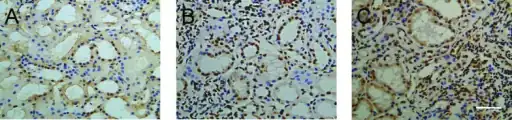

-

a) Apoptotic cell death in IgA nephropathy b,c) scattered distribution in IgA nephropathy. -

Immunostaining showing IgA in the glomerulus of a patient with Henoch-Schönlein nephritis.